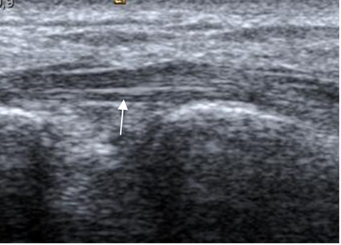

Fig 15. Ligamento tibiocalcáneo normal en ecografía, corte sagital.

Fig 16. Ligamento tibiocalcáneo normal.

Fig 21. Fascia plantar normal en ecografía, corte sagital.